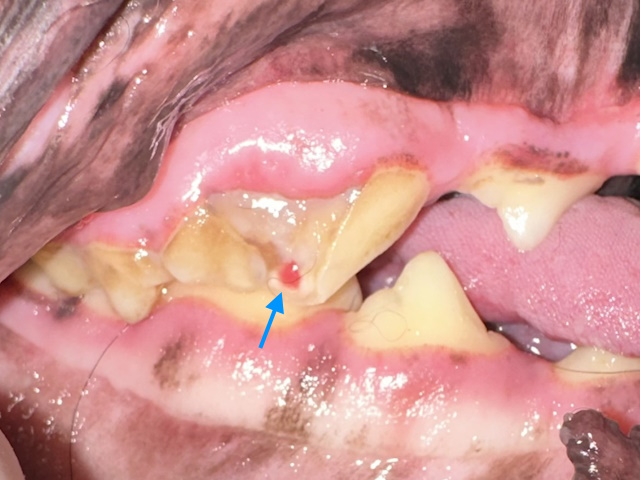

A complicated crown-root fracture that exposes the pulp. The pulp appears pink (blue arrow) indicating the fracture is recent. The fracture extends below the gumline.